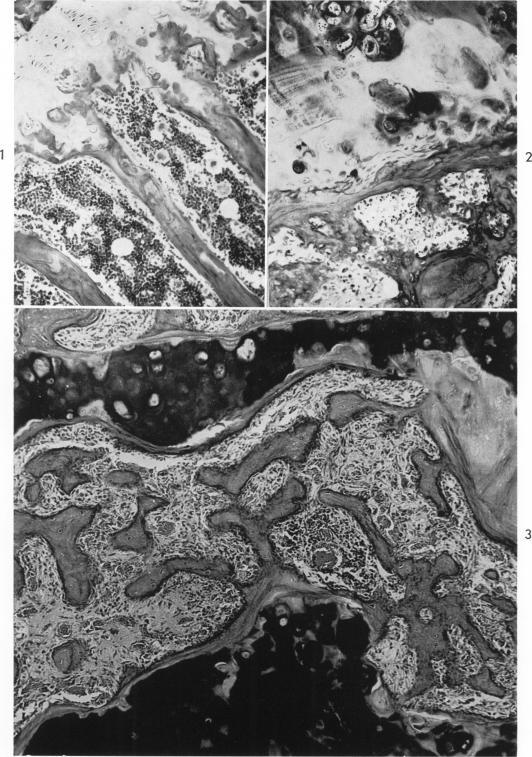

The delayed effects of external gamma irradiation on the bones of rats.

Am J Pathol. 1961 Oct;39(4):455-72.

PMID:13687572

原文链接:https://pmc.ncbi.nlm.nih.gov/articles/PMC1942402/